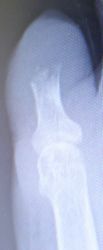

2017年4月4日,当科受診。左第5趾の創部からは骨が露出していたが,感染兆候はなく,第5趾の循環も悪くないようだったため,「露出している骨だけを切除し,創部の乾燥を防いで粘れば,傷はそのまま閉じるかもしれない」と説明。4月5日,飛び出ている骨を骨鉗子で除去し(麻酔は不要だった),ヘモスタパッドで被覆。翌日からはズイコウパッド

の被覆にした。健常者に比べると創面の肉芽形成は遅く,不良肉芽が創面を覆うのみだった。

5月10日,不良肉芽内に浮いてきた腐骨をピンセットで摘んで除去。5月23日からはナイロン糸ドレナージを併用。5月中旬〜8月下旬にかけて創面を覆う肉芽はゆっくりと健常肉芽に置き換わり,9月には創部は自然に閉鎖した,とのことだった。